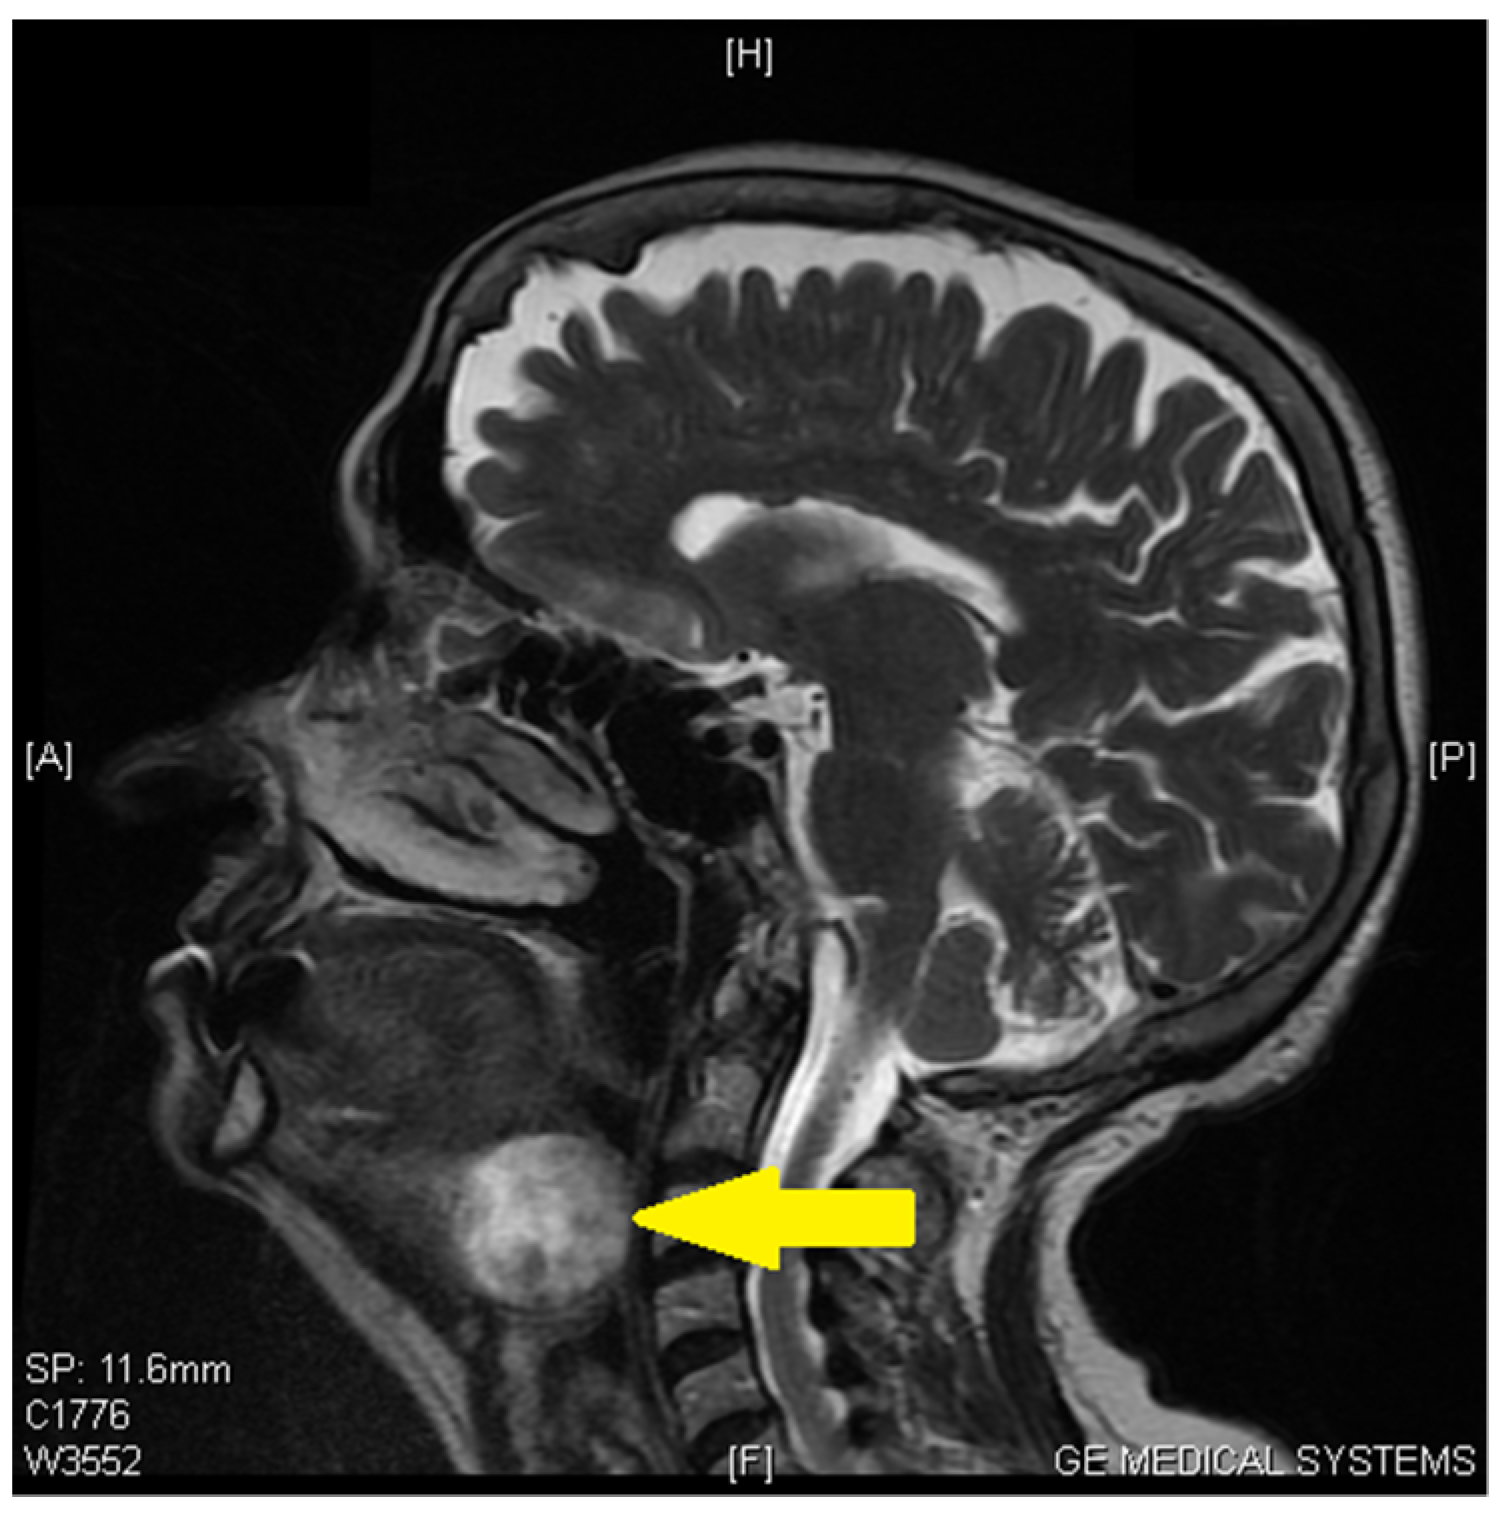

2. Case Report